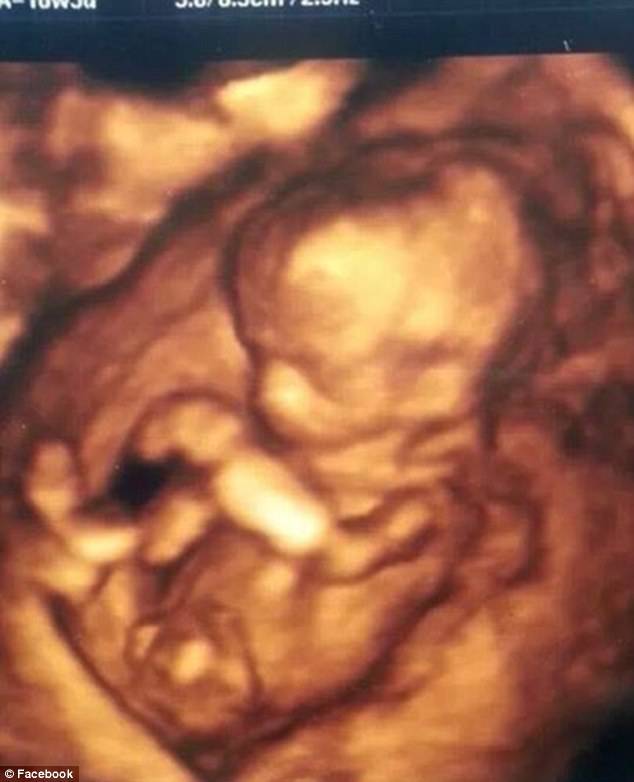

Sharista Giles è una giovane donna rimasta vittima di un grave incidente stradale quando era al 5° mese di gravidanza e a cui i medici avevano dato pochissime speranze di ripresa, ma che è riuscita a stupire tutti.

Nel gennaio scorso i medici hanno quindi fatto nascere il figlio di Sharista con una procedura molto rischiosa: è stato infatti praticato il taglio cesareo per poi trasferire il neonato, che pesava appena 800 grammi, in terapia intensiva neonatale.

Il piccolo prematuro ha combattuto ed è sopravvissuto, ora è un bimbo di 3 chili, ma nel frattempo anche la sua mamma ha tenuto duro e, qualche giorno fa, ha addirittura aperto gli occhi risvegliandosi dal coma.